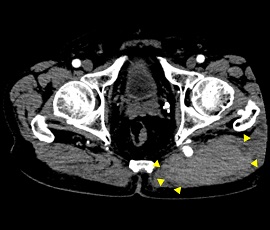

[血管系IVR] 動脈瘤 経動脈的コイル塞栓術

CT画像